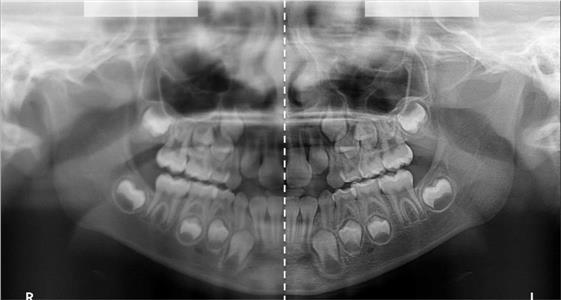

Панорамикс кабинет

За само 13 секунди се добива високо квалитетна ортопантомграфска снимка, странична смнимка, снимка на вилични зглобови, снимка на синуси. Најновиот Kodak панорамикс има 2Д+ програма со која се добиваат 5 пресека во длабочина за прецизна дијагноза и позиција на импактирани заби и други промени. Со квалитетна панорамска снимка нашиот стручен тим ќе постави точна дијагноза и одреди соодветен план на терапија.